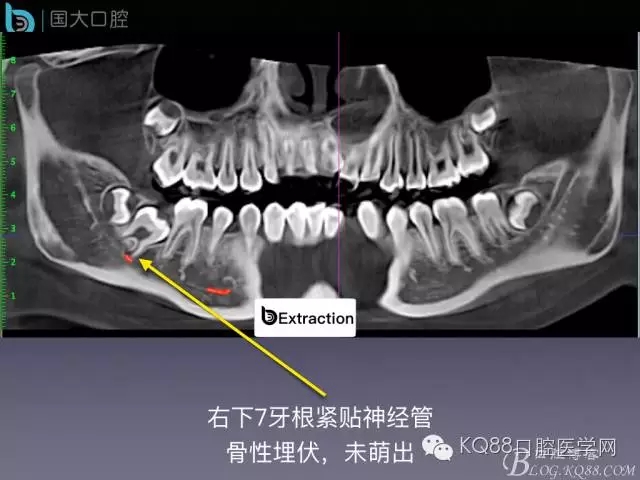

阻生牙的預(yù)防性拔除

- 牙齒拔除適應(yīng)證及第二磨牙遠中齲病